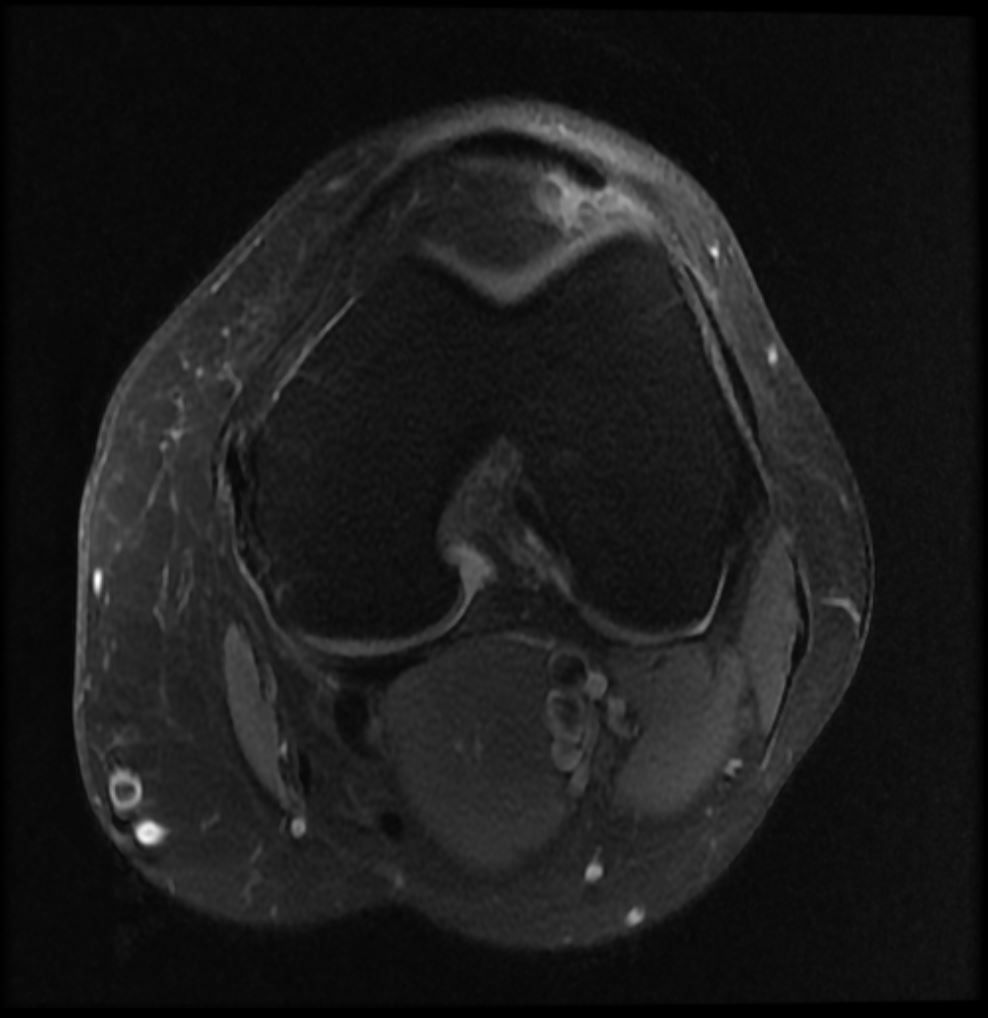

Image IQ Quiz: Young Female with Anterior Knee Pain Post-Injury

Case: Young female presents with anterior knee pain post-injury.

What most likely represents the imaging finding?